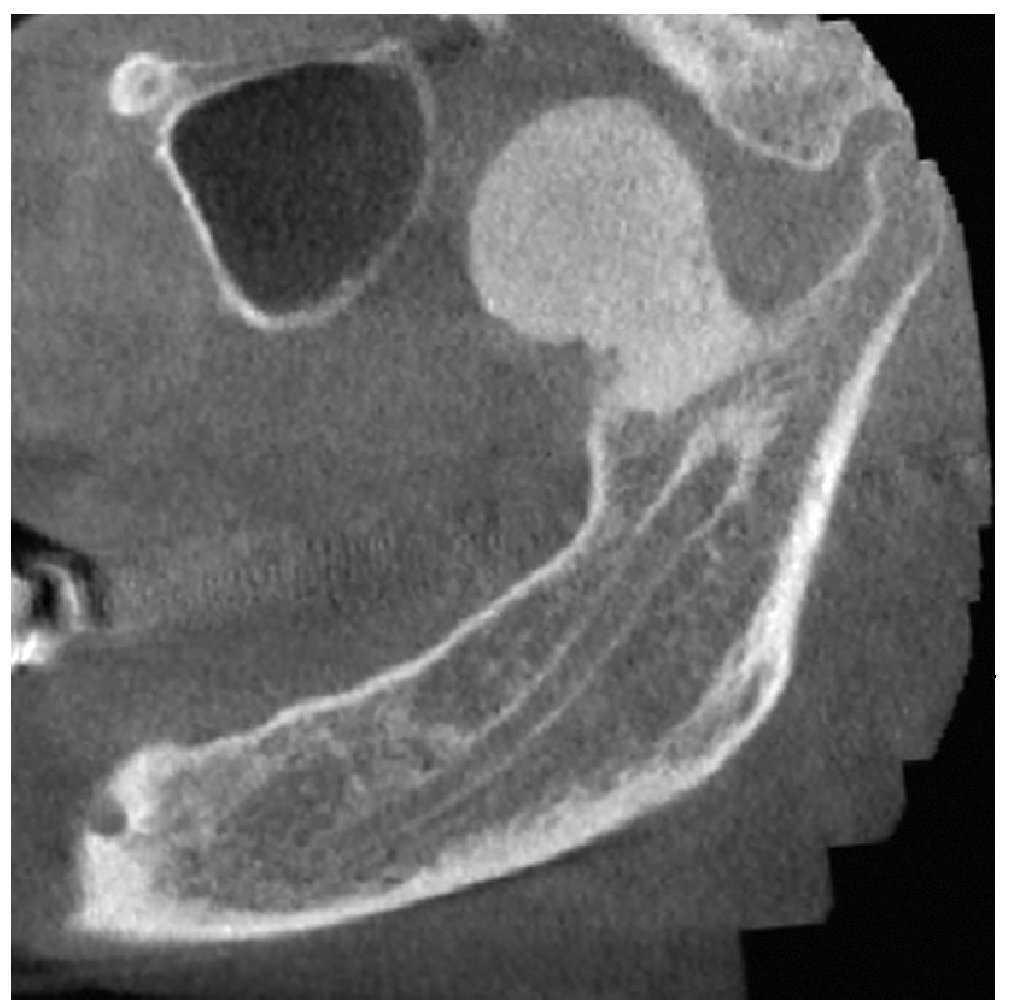

La radiografía panorámica (fig. 1) mostró una estructura de tejido óseo, densa, homogénea, con forma de hongo, bordes bien definidos y un diámetro de varios centímetros. La lesión parecía originarse en un área por encima del agujero mandibular. Un TAC de haz de cono (figs. 2 a 5) reveló la presencia de una lesión homogénea osteodensa de 3 x 3 x 2,7 cm que crecía a partir de un pedúnculo en la cara lingual de la escotadura mandibular. La circunferencia anterior alcanzaba casi a la apófisis coronoides.

Figura 4. Imagen sagital de un TAC de haz de cono.